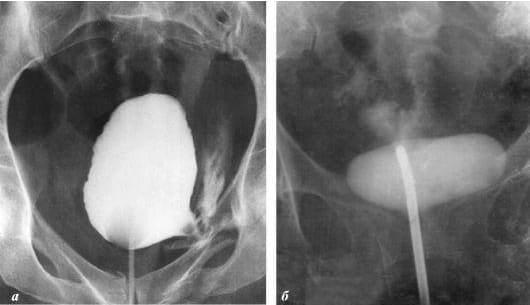

Chciałabym pokazać wam kilka zdjęć, żebyście na własne oczy przekonali się, co dzieje się z układem moczowo-płciowym i innymi organami mężczyzn, którzy nie uprawiają seksu.

Tak wygląda zapalenie gruczołu krokowego wywołane zastojem spermy (gdy jądra nie są opróżniane). Utrzymujący się stan zapalny prowadzi do łagodnego rozrostu prostaty, a następnie do raka (według statystyk, 38% mężczyzn umiera z jego powodu). Zawsze tak się dzieje w przypadku braku seksu i dlatego łagodny rozrost prostaty nazywany jest chorobą ludzi starszych.

Rak gruczołu krokowego u mężczyzny w wieku 58 lat. Przyczyna – wydłużająca się abstynencja (od około 51 roku życia). Pacjent zmarł.